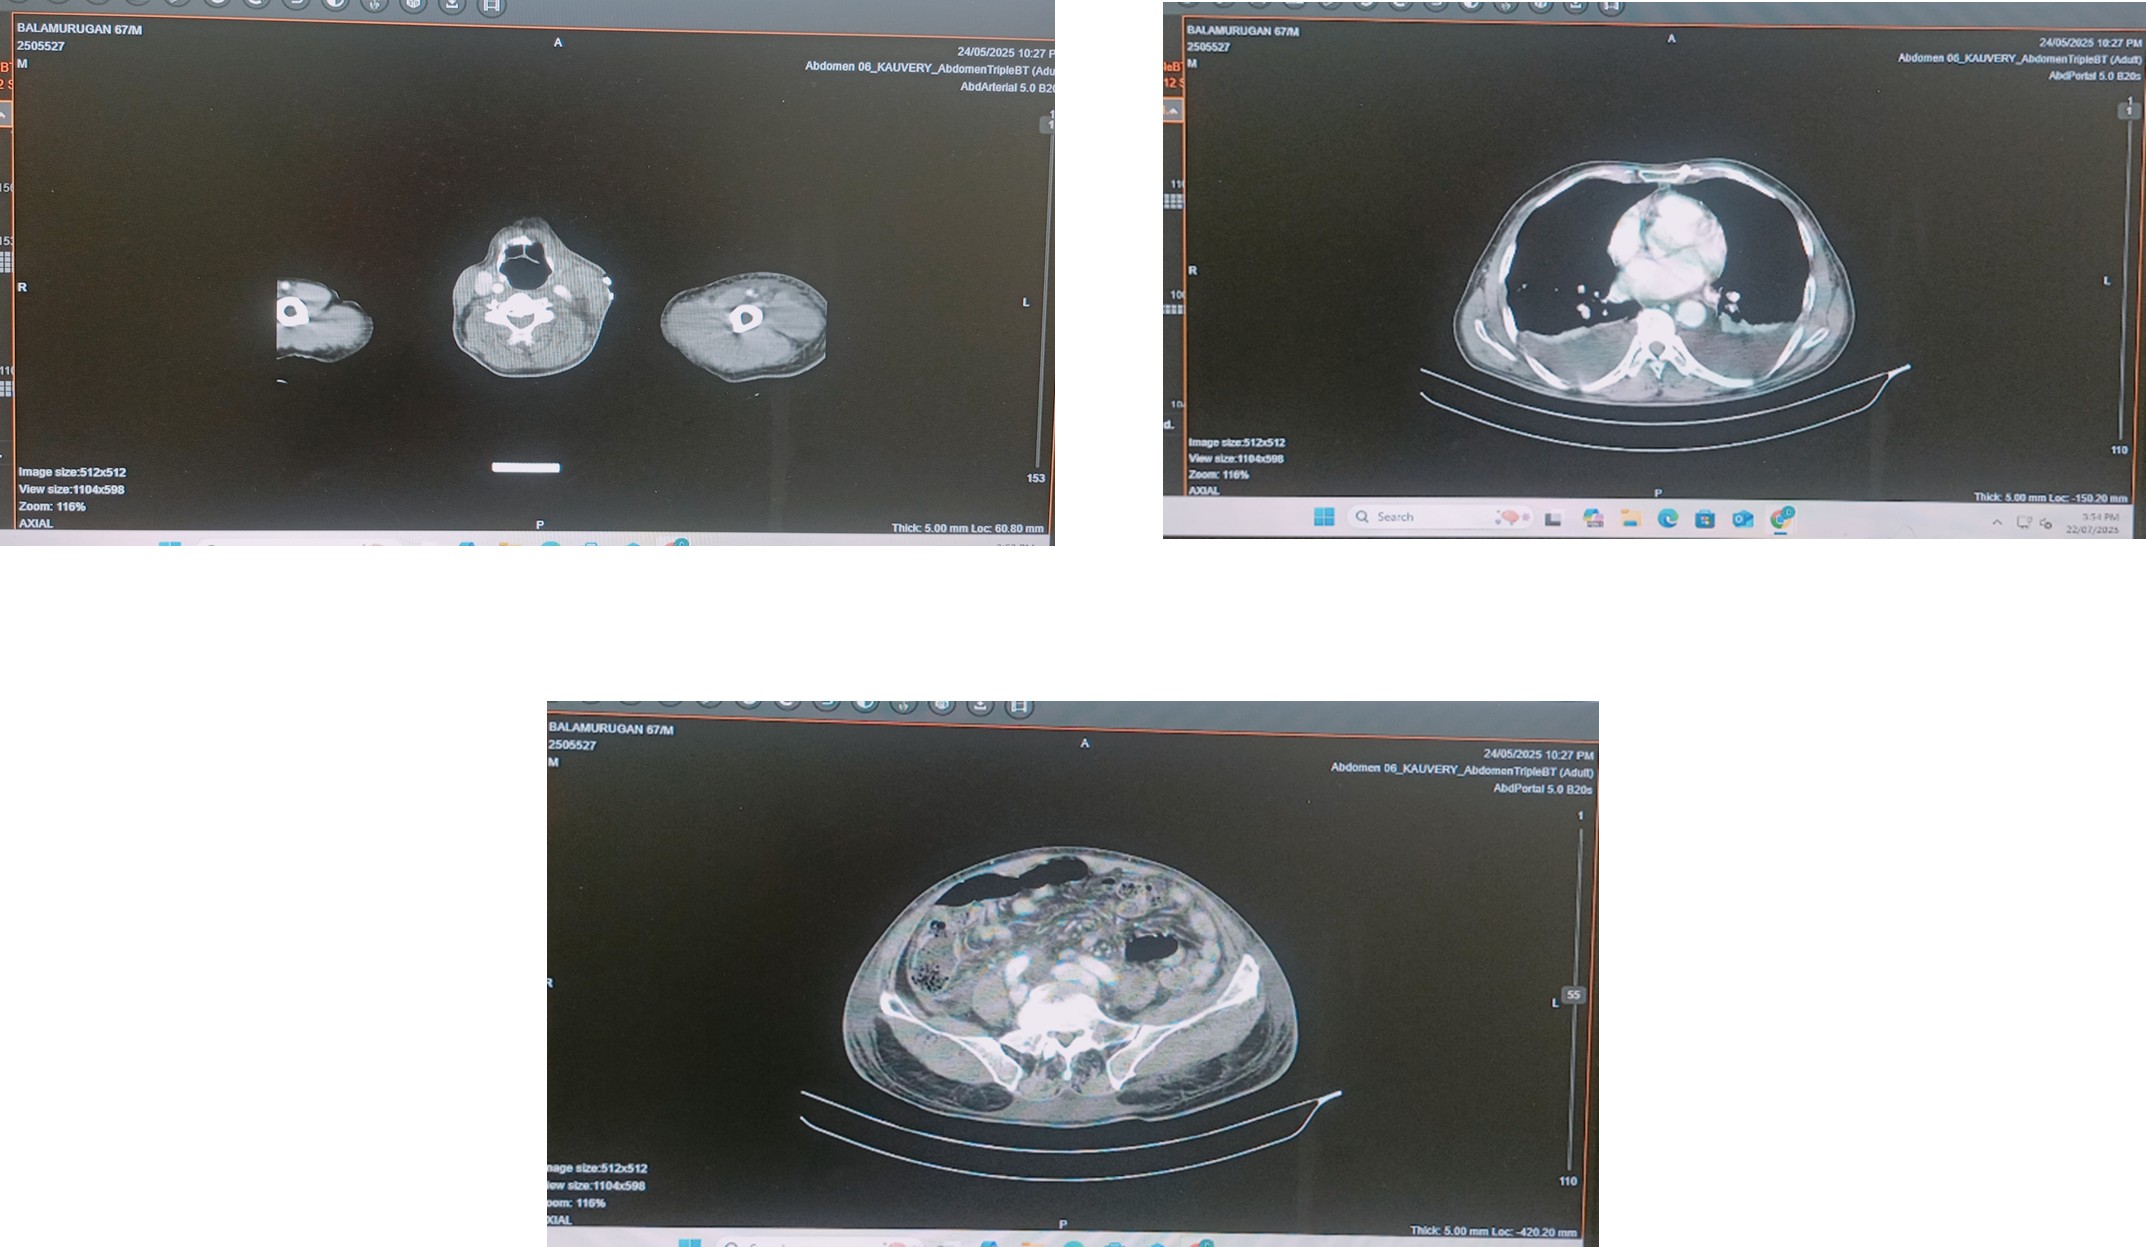

Patient had abdomen pain CT abdomen (17-05.2025) taken that shows bilateral contracted kidneys, dilated fluid filled small and large bowel loops with right inguinal hernia no obvious evidence of obstruction at present, prostatomegaly.

Patient had abdomen distension and had pain (6/10), and did not pass stool for 2 days in view of that CT abdomen and pelvis done on (24.05.2025) it showed large hematoma in the paraaortic region adjacent to head of pancreas with surrounding inflammatory change

Advice CT Angio to R/O pseudo aneurysm / direct extravasations of contrast bilateral medial renal disease

Moderate ascites, right inguinal hernia, mild prostomegaly, bilateral pleural effusion with collapse of bilateral lower lobes, and no evidence of pneumoperitoneum / bowel obstruction.

Multislice CECT – Abdomen and Pelvis CECT (24.05.2025)

Large hematoma in the Para aortic region adjacent to the head of pancreas causing compression and displacement of the adjacent GDA and its branches. No obvious evidence of direct extravasation of contrast /pseudoaneurysm. Bilateral renal simple cysts, moderate ascites with diffuse abdominal wall edema, right inguinal hernia with mild prostomegaly. Bilateral pleural effusion with collapse of bilateral lower lobes.